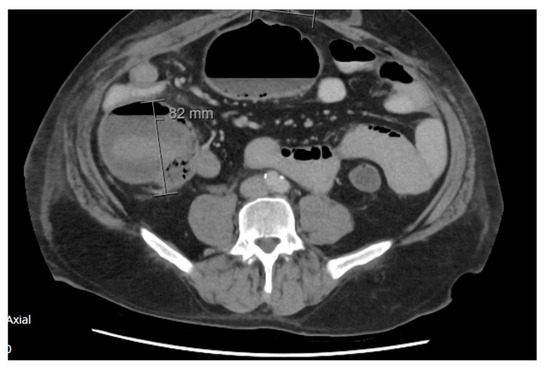

2.1.1. Case 1